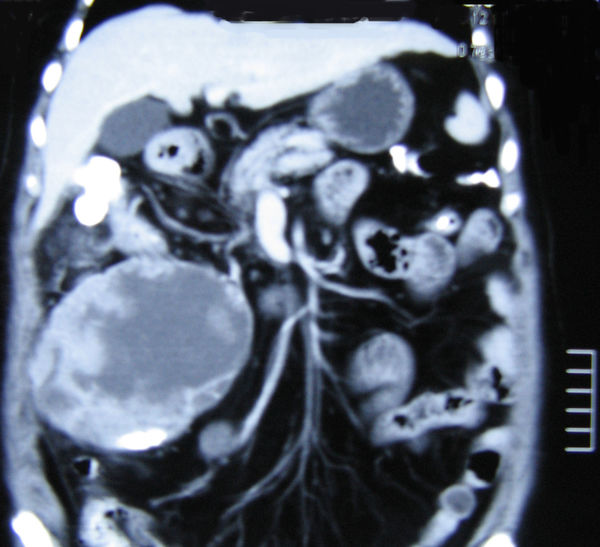

患者 女,73岁。因右肝肿瘤介入化疗术后2个月,腹胀痛伴发热10d入院。2个月前患者自行发现右上腹一巨大包块,CT检查提示肝右叶16cm ×13cm ×10cm 巨大占位,强化后考虑为肝恶性肿瘤,即行肿瘤穿刺活检。病理诊断:低分化细胞癌,行经肝动脉栓塞化疗2次。10d前突感腹痛,伴有发热。体查:贫血貌,皮肤巩膜无黄染。右上腹巨大包块,下达髂前上棘上方,质韧、囊实性,稍有活动感,无压痛。肿瘤标志:CEA,CA199,AFP检测均在正常范围。乙肝血清检查示阳性。复查CT示:肝脏右后叶外生性巨大肿块,大小约25cm ×20cm ×15cm,呈不规则分叶状、囊实性,密度不均,散见碘油沉积高密度影,中心呈片状低密度区,增强后实质部分动脉济南军区总医院肝胆外科张建平

期不均匀强化,邻近结肠、十二指肠受压、移位,界限不清。诊断:原发性肝癌。行肝Ⅵ 段切除+肿瘤切除+结肠部分切除术,术中证实肿瘤源于右后叶下缘,呈外生性生长。术后病理:肉瘤样肝癌伴囊性变、出血。免疫组化:CK19(-),AFP(-),hepatocyte?1(-)。术后12d痊愈出院。随访5个月,情况良好。